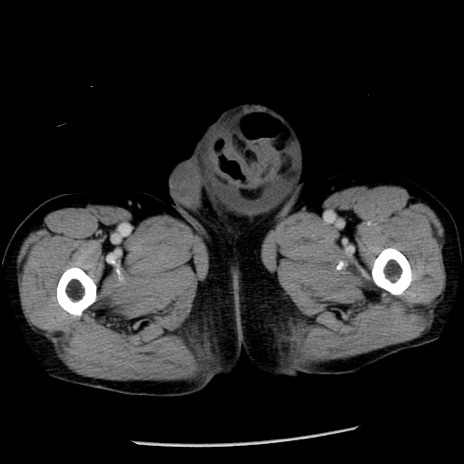

症例26(横断像)

【症例】80歳代男性

【主訴】嘔吐

【現病歴】昨晩2回嘔吐あり、今朝になっても嘔吐あり。来院。

【既往歴】胃潰瘍

【身体所見】意識清明、BT 37.6℃、BP 166/95mmHg、HR 100bpm、SpO2 97%、腹部:平坦・軟、腸蠕動音聴取良好、圧痛なし。

【データ】WBC 21900、CRP 1.46